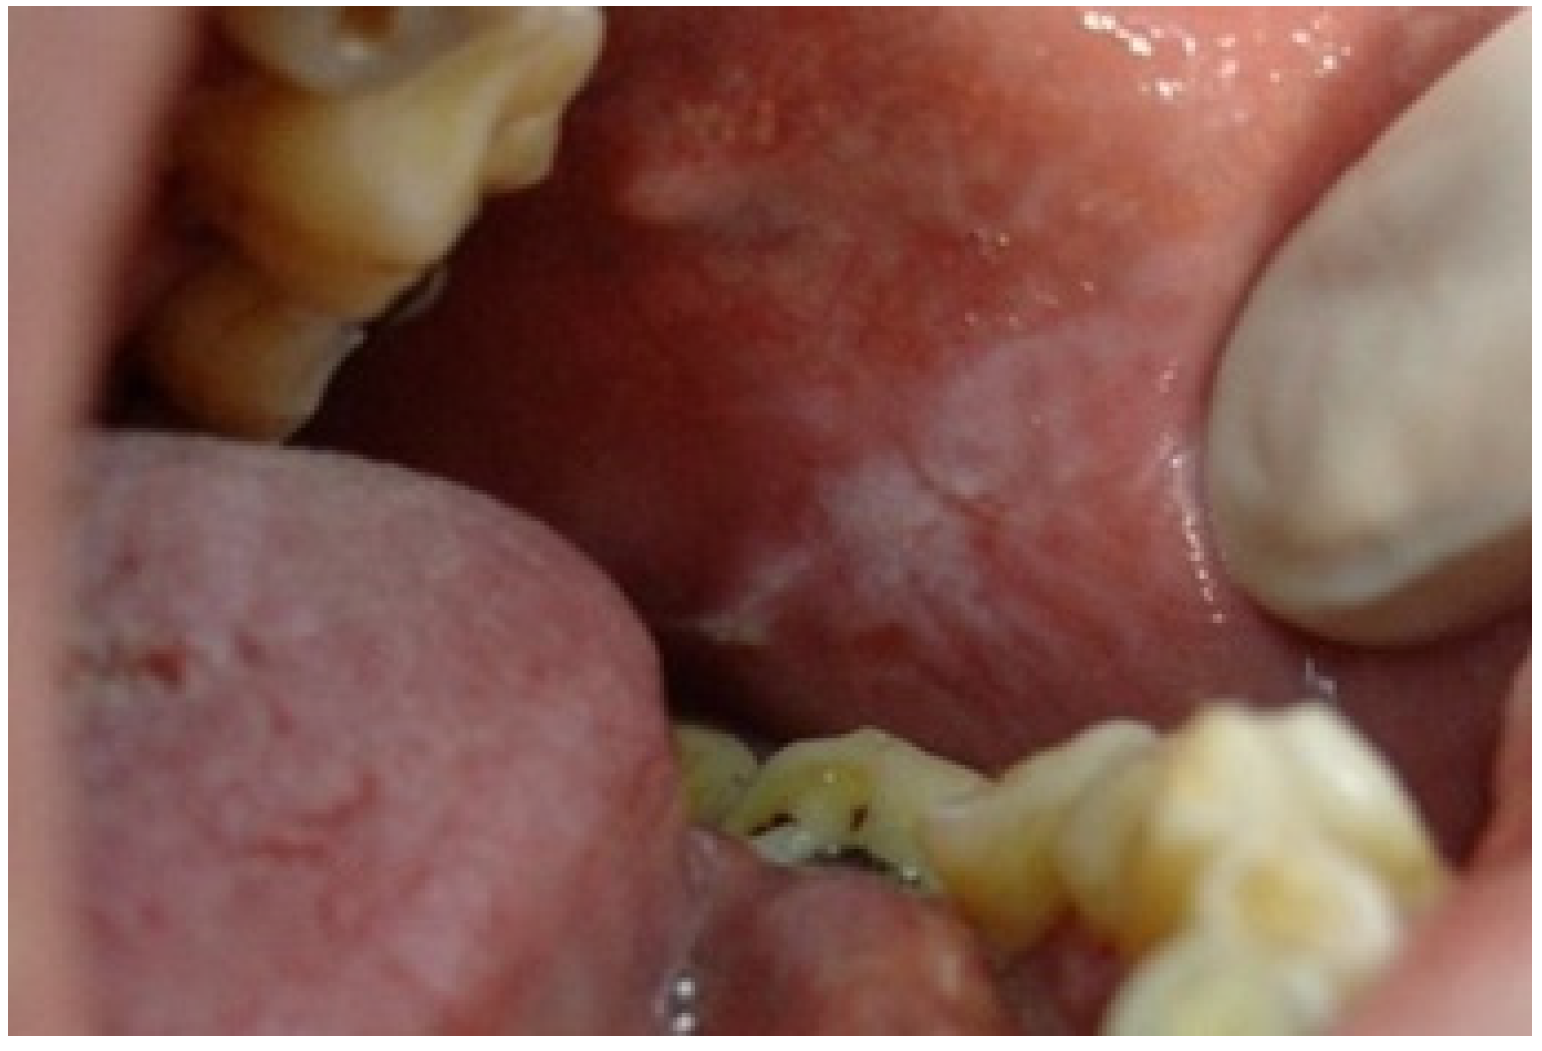

The third most frequently observed mucosal lesion in studied population was Morsicatio buccarum (MB). As pictured in Figure 5, this condition is characterized by a rough, whitish, shredded oral mucosa and develops due to the parafunctional, habitual biting/chewing of the buccal mucosa. The overall frequency of its occurrence was 9.1%, similar to what was observed among 0–12 y/o Brazilian children (8.4%) [27]. Jimenez et al. also found high incidence of this disorder, amounting 15.87%, among Venezuelan children aged 2–17 [28]. In many other researches, Morsicatio buccarum was diagnosed as one of the most common OMLs in children, but with varying incidence [2,3,17]. Nevertheless, it should be underlined that in many cases MB was included in the group of trauma-associated lesions (along with erosions, ulcers, etc. caused due to injuries or dental and orthodontic treatment), so it is difficult to directly compare the results [1,9,10,20], however the incidence rate of such compiled diagnoses was also very high in each study group. In our investigation, MB was the second most frequent diagnosis among boys and the 5th most commonly recognized in females, but there was no significant difference between the genders. This correlation was also observed in the work of Jimenez-Palacios et al. [28]. The number of MB cases was significantly increasing with age (p = 0.04), which was also observed by other researchers [2,9,10,27,28]. This observation can be explained that MB is considered as a parafunctional activity that develops in response to higher psychological overload, higher stress and anxiety, especially the one related to school and studying stress, which intensifies with the age of pupils [9,29,30,31].

Figure 5.

Morsicatio buccarum on the left buccal mucosa of a teenage boy. In this patient, the lesion was observed bilaterally in an atypical location in the midpart of the buccal mucosa along with occlusal line. The mucosa is white, thickened, shredded, and combined with zones of the erythema and erosion.